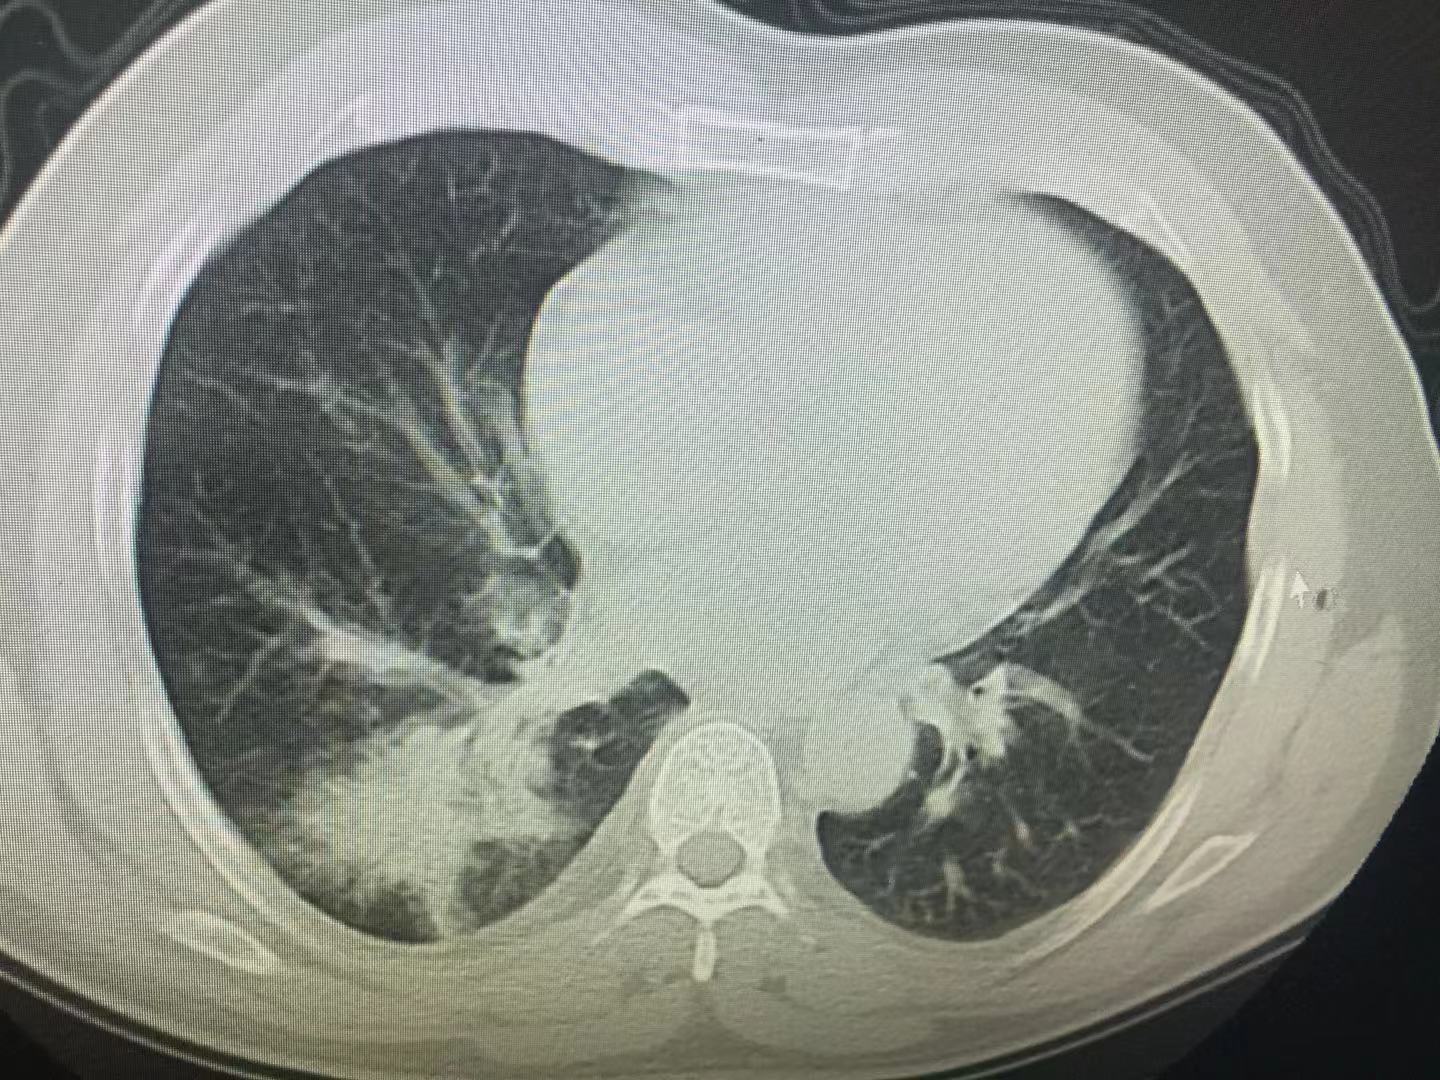

CT

CT(Computed Tomography),学名电子计算机断层扫描。断层扫描简而言之是将人体横切成一片一片的去观察,基本上只要超过1mm的结节都可以清晰的出现在图像上,对肺组织的纹理及结构变化更为清晰。对于一些微小病灶可以早发现早诊断。一些在X光片体检时发现的小阴影都可以通过CT进行确定是否为病变还是正常组织结构。主要可以排查肿瘤和一些肺组织病变(如间质性肺疾病早期容易被忽视,胸部CT尤其是高分辨率HRCT是诊断这类疾病的首要方法)。但CT检查的辐射要高于X光,价格也较为昂贵。